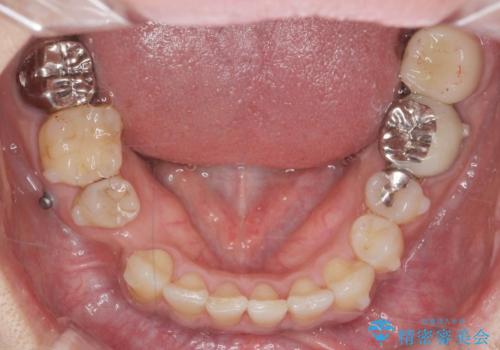

- 治療計画

- 長年虫歯の治療を受け続けたことで銀歯・コンポジットレジン修復だらけになってしまい、今後の見た目や歯を大切にするためにセラミック治療矯正治療を希望され来院されました。

マイクロスコープを用いた精密根管治療やセラミック治療、マウスピース矯正治療を一つの医院で行うことのできる当法人ならではの総合歯科治療を実践していきます。